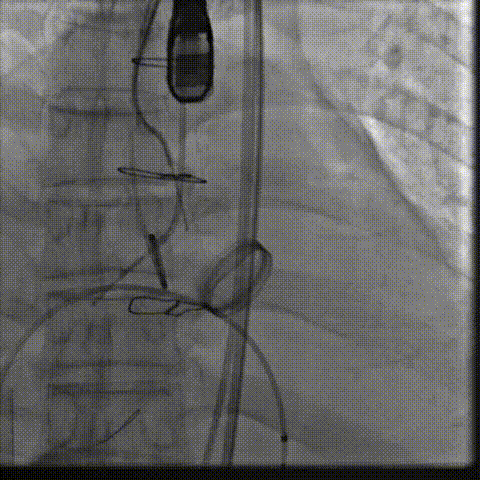

在右股动脉穿刺建立通路后,将右冠送入冠脉保护,后顺利送入大鞘,经食道超声及血管造影确认路径稳定,将ProStyle A ® AV32号瓣膜精准释放于目标位置(瓣下2mm),超声显示无瓣周漏,平均跨瓣压差4mmHg,心功能明显改善,患者生命体征平稳。

缓慢释放瓣膜

最终造影,位置形态良好,冠脉充盈良好

术后超声: 显示瓣膜呈现较好的圆形,最大流速133cm/s,平均跨瓣压差显著降低至4mmHg,瓣周无反流。